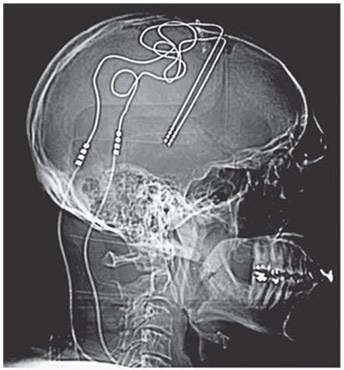

Эти идеи — не просто теоретизирование. Ученые с подходящим оборудованием могут менять аффект людей с помощью прямого манипулирования зонами распределения ресурсов, которые выдают прогнозы. Хелен С. Мейберг, пионер-невролог, разработала терапию с глубокой стимуляцией мозга для людей, страдающих от терапевтически резистентной депрессии. Эти люди не просто переживают страдания от значительных депрессивных эпизодов, — они страдают, пойманные в ловушку ненависти к себе и бесконечных мучений. Некоторые из них едва могут двигаться. Во время хирургического вмешательства Мейберг работала с группой нейрохирургов, которые сверлили маленькие отверстия в черепе и устанавливали электроды в ключевую прогнозную зону в интероцептивной системе пациента. Когда нейрохирурги включали электроды, пациенты Мейберг сообщали о немедленномоблегчении страданий. По мере того как электрический ток включался и выключался, волна страха у пациентов появлялась и отступала синхронно со стимуляцией. Замечательная работа Мейберг, видимо, впервые в истории науки показала, что непосредственное стимулирование человеческого мозга надежно меняет аффективные чувства людей, что потенциально ведет к новым методам лечения психических заболеваний [188].

Иллюстрация к книге — Как рождаются эмоции. Революция в понимании мозга и управлении эмоциями [i_020.jpg]

Рис. 4.6. Глубокое стимулирование мозга